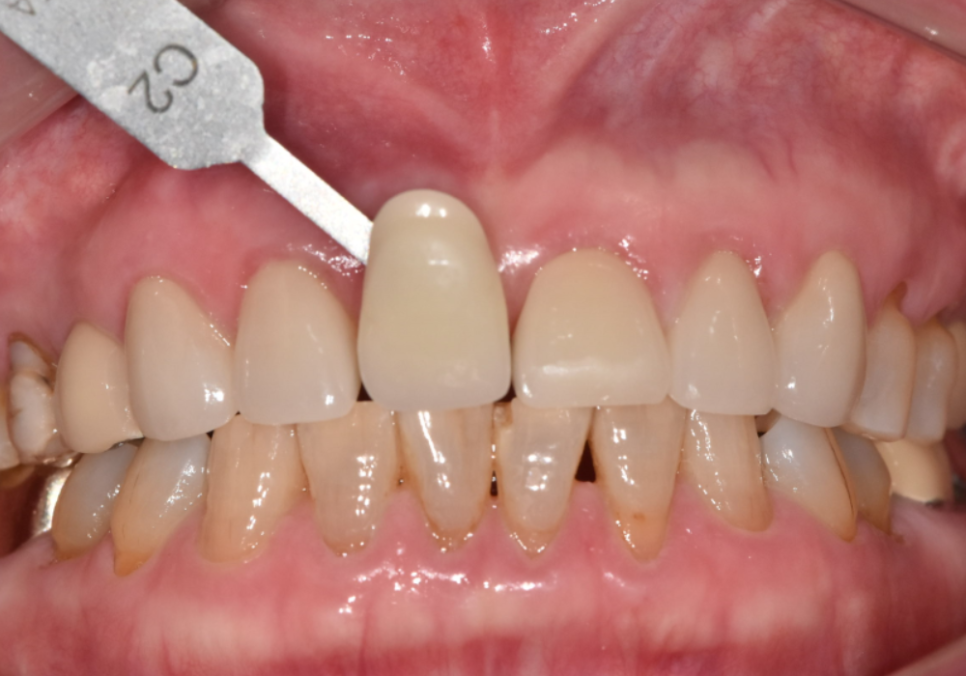

여기서 가장 공을 들여야 할 부분은 무엇일까요?

바로 기존에 먼저 해두었던

다른 앞니 보철물들과

색상을 감쪽같이 맞추는 일입니다.

위의 사진처럼 새로 만든 치아가

유독 하얗게 둥둥 떠 보인다면

아무리 튼튼하게 잘 심었어도

성공적인 치료라고 말하기는 어렵겠죠.

주변 치아들과 마치 원래부터 하나였던 것처럼

자연스럽게 어우러지도록 만드는 데

가장 많은 정성을 쏟았습니다.